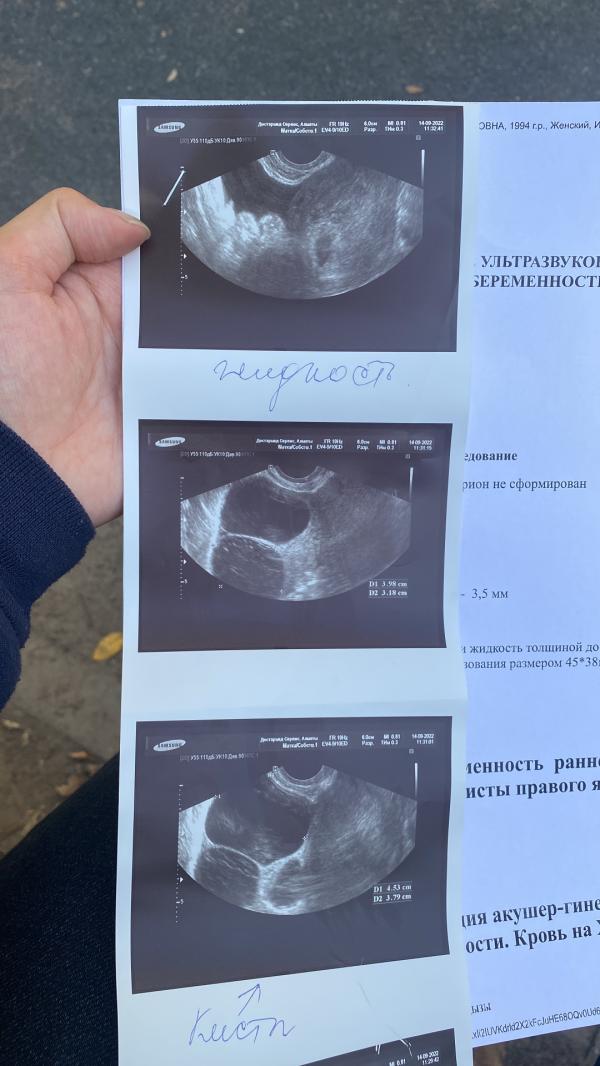

Так как мы планировали уже давно, до беременности я все болячки пролечила, была жидкость за маткой, мазок плохой, но на последних узи и результатах мазка всё хорошо. И вот мы, наконец, решились, забеременела, а тут такое. 11.09 пошла кровь (6 неделя), не так много, но для имплантационного кровотечения вроде поздновато, поехали в 12 гор.больницу, беременность подтвердили, на узи все норм сказали, но эмбриона ещё нет. Гинеко...